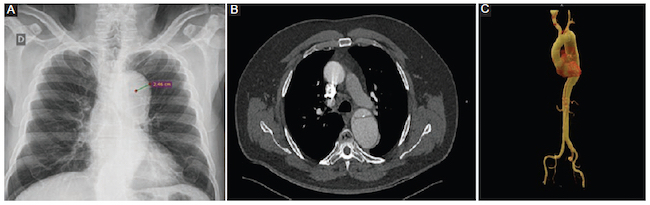

Distancia entre una calcificación intimal y el contorno externo de la pared aórtica mayor de 6 mm (Fig. 3).

El diagnóstico tomográfico de DA se realizó teniendo en cuenta los siguientes criterios: presencia de colgajo de disección, desplazamiento interno de las calcificaciones de la íntima, colgajo de la íntima visible, evaluación de la presencia de complicaciones (rotura hacia mediastino-pleura-pericardio, extensión y compromiso de ramas principales). Se clasificó la DA, según los criterios de Stanford, en tipo A (con involucro de la aorta ascendente) o tipo B (distal a la arteria subclavia izquierda)

Se calculó una media para el ancho mediastínico máximo de 9,6 cm y para el ancho mediastínico izquierdo de 7 cm en pacientes con DA. En los pacientes sin DA, la media del ancho mediastínico máximo fue de 8,1 cm y la del ancho mediastínico izquierdo de 5 cm (Tabla 3).

Por otro lado, el derrame pleural izquierdo (p = 0,315), el desplazamiento de las calcificaciones parietales a una distancia mayor de 6 mm (p = 0,216) y la desviación de la tráquea a la derecha (p = 0,361) no fueron estadísticamente significativos para el diagnóstico (Tabla 4).